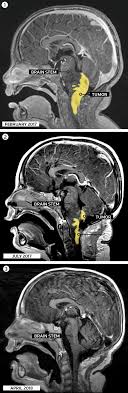

Childhood Ependymoma Treatment Pdq Patient Version National Cancer Institute from nci-media.cancer.gov Most exposures that cause cancer, such as tobacco smoke, somehow damage dna. They can also indirectly damage cells by pushing on other parts of the brain. Astrocytoma is the most common type of glioma diagnosed in children. The exact cause of brain tumor is unknown till today. Brain tumors and other nervous system tumors make up about 27 percent of childhood cancers. Some kids who have certain genetic conditions have a greater chance of developing brain tumors. Up to 10% of all cancers in children are caused by a heritable (germline) mutation (a mutation that can be passed from parents to their children). The symptoms of childhood brain stem glioma vary and often depend on the child's age and where the tumor is located.

See your gp if your child has any symptoms of a brain tumour to get them checked over. Many children with a brain tumor experience headaches before their diagnosis. Most brain tumors in children start in the lower parts of the brain, such as the cerebellum or brain stem. When a child develops a brain tumor, early diagnosis is essential. Brain tumors can directly destroy brain cells.

The signs and symptoms of childhood brain and spinal cord tumors are not the same in every child.

Brain and spinal cord tumors are a common type of childhood cancer. Some kids who have certain genetic conditions have a greater chance of developing brain tumors. What is a brain tumor? Primary brain tumors involve a growth that starts in the brain, rather than spreading to the brain from another part of the body. Tumours that start in the brain are called primary brain tumours. The symptoms of childhood brain stem glioma vary and often depend on the child's age and where the tumor is located. Brain tumors are the most common solid tumors affecting children and adolescents, with close to 5,000 children diagnosed each year.; Brain tumors and other nervous system tumors make up about 27 percent of childhood cancers. Many tumors are more common at a certain age. The signs and symptoms of childhood brain and spinal cord tumors are not the same in every child. The tumor may start in your child's brain or travel to his brain from another body area. Examples include nerves in your child's skull, his pituitary gland, or the membranes that cover his brain. In general, brain tumors in children are very rare.